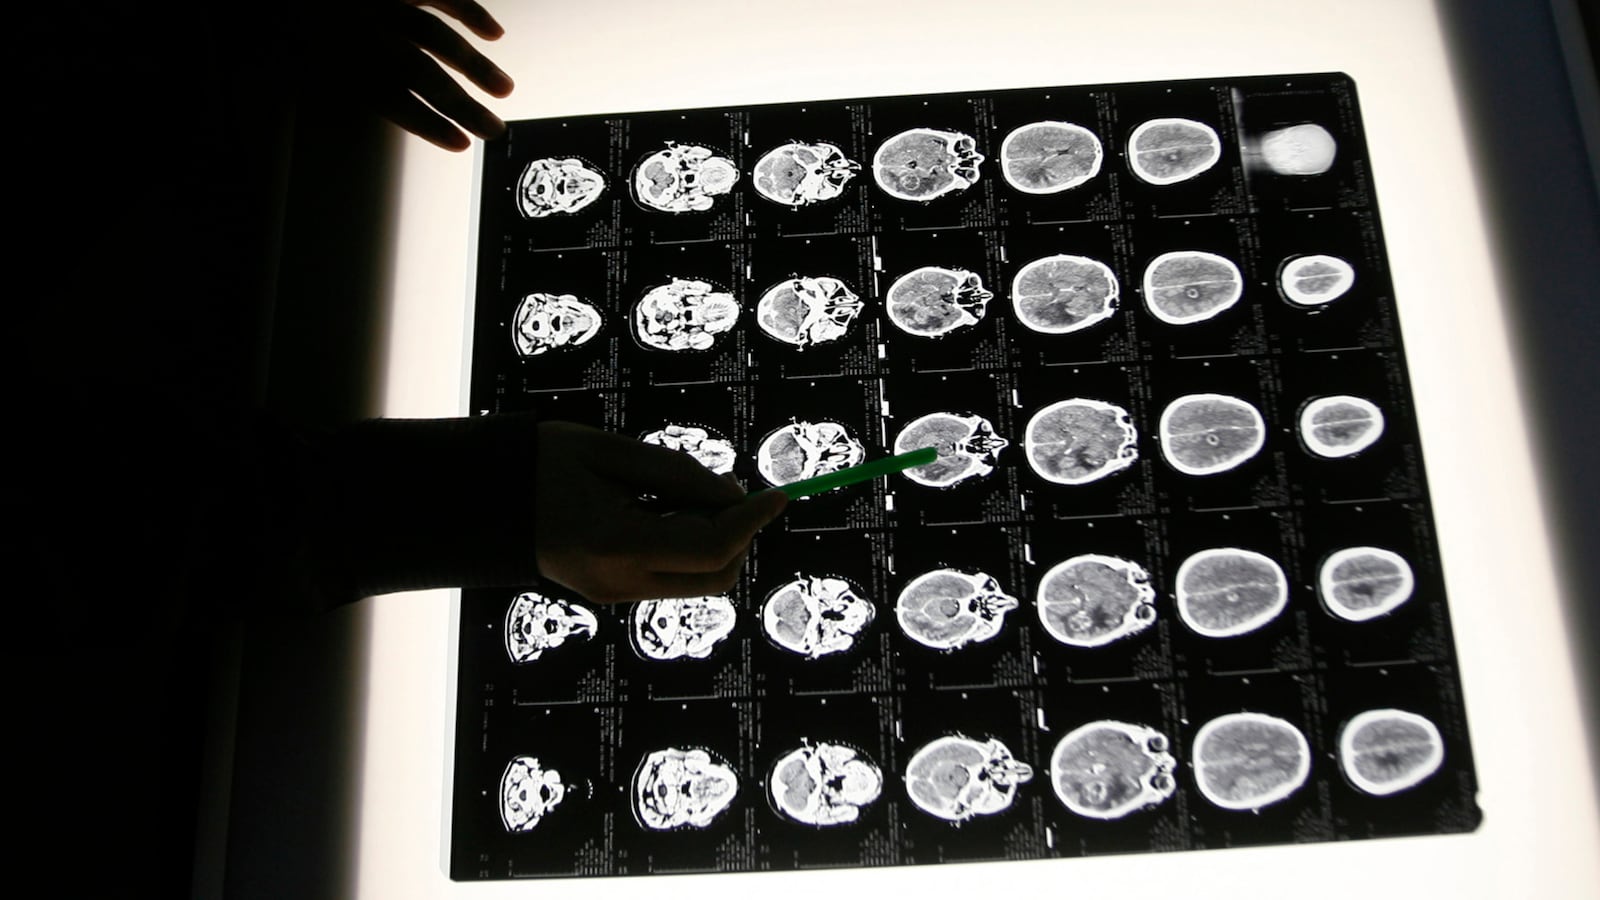

A woman died from a brain-eating amoeba after using a neti pot with tap water to clear her sinuses, USA Today reports. The 69-year-old Seattle woman was reportedly told by her doctor to use a neti pot twice daily. About a month after using the device with filtered tap water, the woman found a “quarter-sized red rash” on the right side of her nose, according to a report from the International Journal of Infectious Disease. One year after the rash developed, she reportedly had a seizure, and doctors found a half-inch lesion on her brain. When doctors removed the lesion, they noticed it had “unusual characteristics” and sent it to Johns Hopkins University for further analysis. The woman’s left arm and leg reportedly became numb, and she remained in an “altered mental” state days after surgery. When a neuropathologist finally started treatment for an amoebic infection, it was reportedly too late and the woman’s condition failed to improve. Her family eventually took her off life support.